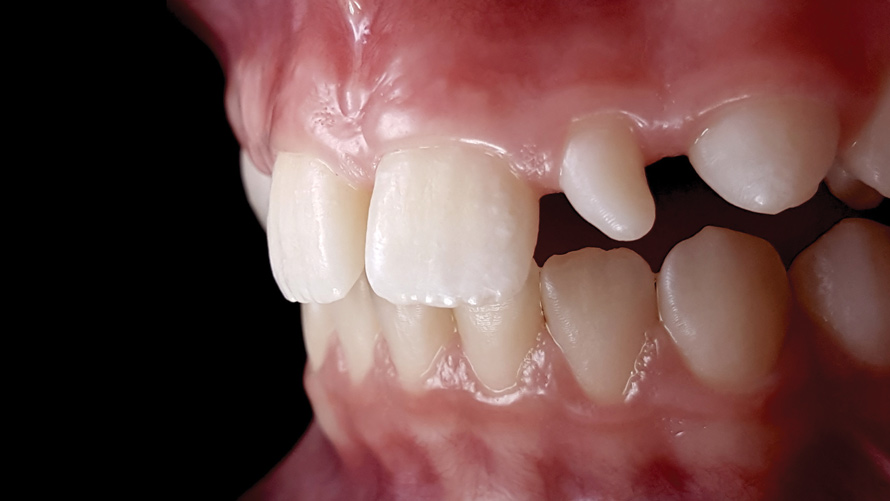

(10.) Preoperative esthetic case documentation using a smartphone and an EALS device.

Figure 10

(11.) Preoperative esthetic case documentation using a smartphone and an EALS device.

Figure 11

(12.) Intraoral photographs taken with a smartphone and an EALS device for orthodontic evaluation.

Figure 12

One of the main advantages that smartphone cameras have over DSLR cameras is that nearly everyone is already very familiar with the technology; therefore, the incorporation of these devices into everyday practice does not require learning a new and unfamiliar skill set. The task of producing a series of high-quality clinical photographs for routine examinations (Figure 8), esthetic treatment planning (Figure 9 through Figure 11), or specialty care (Figure 12 and Figure 13) can be delegated with confidence to any staff member during the patient's initial office visit and will generally require less than 5 minutes of time to complete. When a DSLR camera is used, evaluation of the intraoral images either takes place on the small viewfinder built into the camera or necessitates the physical removal of the memory card from the camera to downloaded the images onto a computer for review. An added bonus of smartphone dental photography is that the phone's screen now replaces the much smaller viewfinder of a DSLR camera and provides the clinician with the ability to view and zoom into the patient images on a 5- to 6-inch, high-definition display.